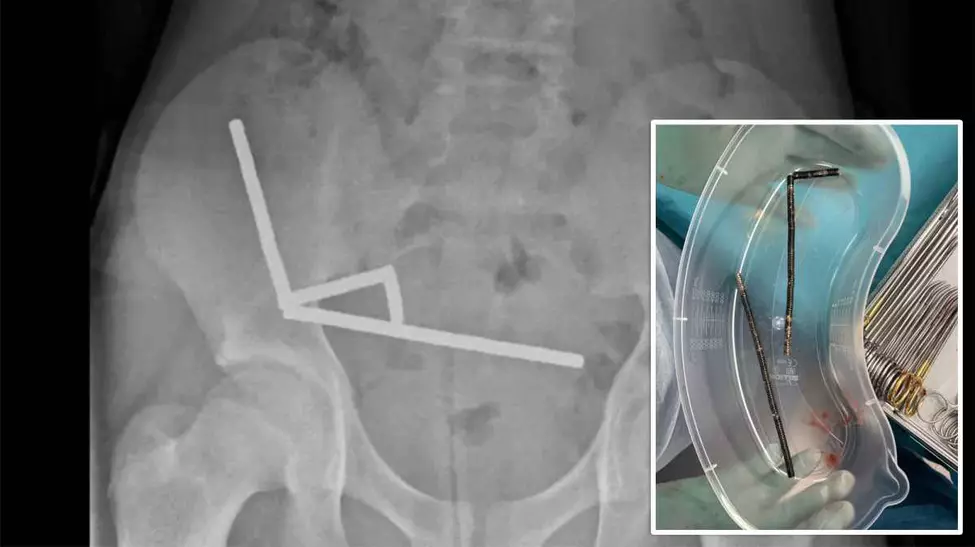

Magneti

Magnetii sunt adesea gasiti acasa, pe ornamente de frigider, brelocuri de chei, lanturi sau ca parte a jocurilor si jucariilor magnetice. Chiar daca sunt mici, acestia pot provoca multe daune tractului gastrointestinal al unui copil. Daca un copil inghite mai multi magneti, acestia pot intra in contact unul cu celalalt in interiorul tractului digestiv, pot impiedica alimentarea cu sange si pot provoca probleme grave de sanatate si chiar moartea.